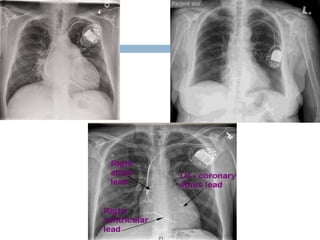

Pacemakers

 Single chamber – tip in right appendage or

right ventricular apex

 Dual chamber – tip in right atrium and right

ventricular apex

 Biventricular – tips in right atrium ,ventricle and

coronary sinus

• 90.

Pacemakers  Single chamber– tip in right appendage or right ventricular apex  Dual chamber – tip in right atrium and right ventricular apex  Biventricular – tips in right atrium ,ventricle and coronary sinus